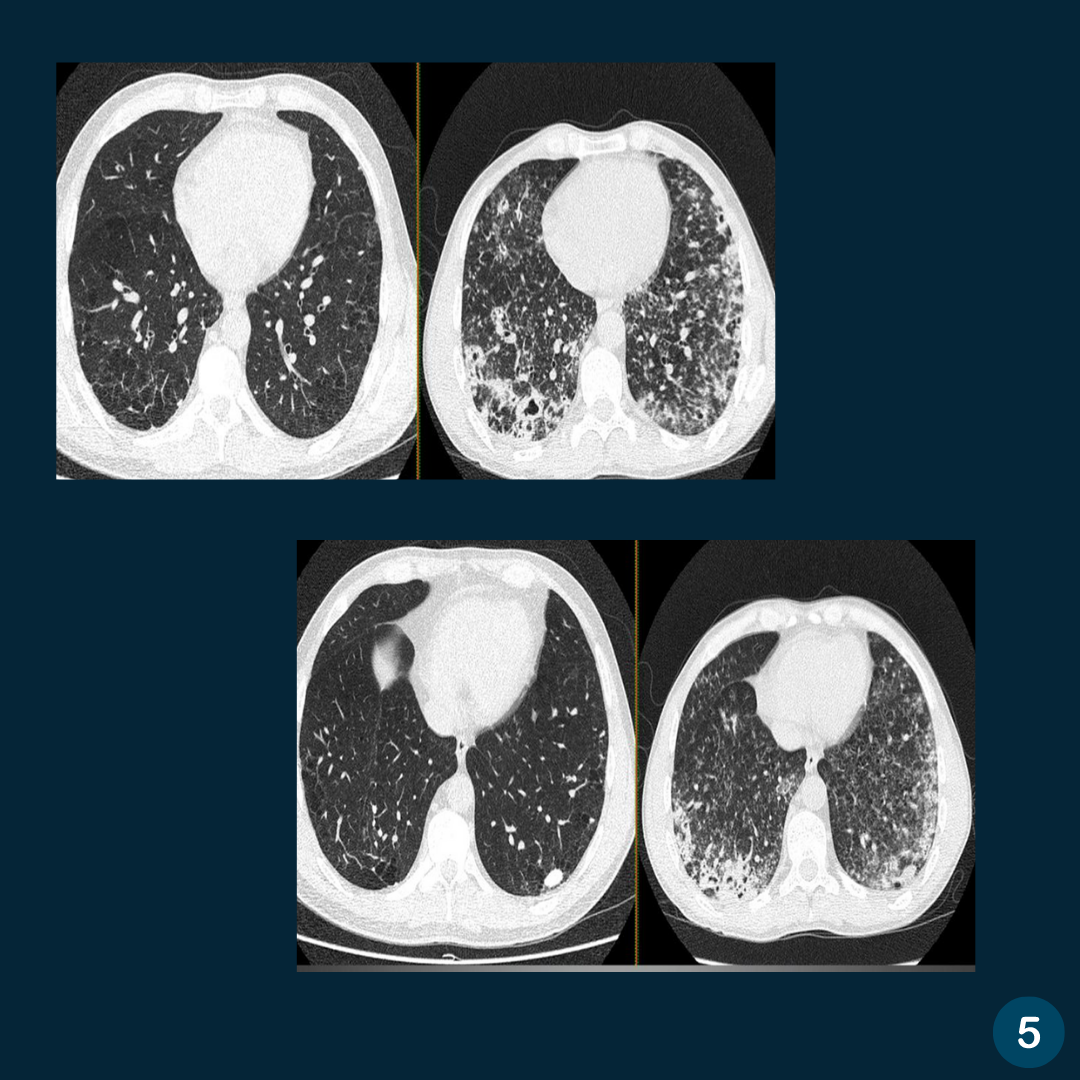

Caso do Dia – Tosse crônica

Contribuição – Dr. Thales Zerbato Tetilla